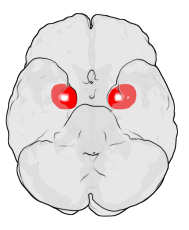

لوزة المخ amygdalaecorpus amygdaloideum؛ باللاتينية، من اللاتينية ἀμυγδαλή, amygdalē، 'almond', 'tonsil'[1])، مدرجة في تشريح گراي باسم nucleus amygdalæ، هي مجموعتين من النوى على شكل لوزة تقعان في المنطقة العميقة والوسطى داخل الفص الصدغي في المخ لدى الثدييات المتطورة، ومنها البشر.[2] أظهرت الأبحاث أن للوزة المخ دوراً أساسياً في معالجة الذاكرة، صنع القرار، وردود الفعل العاطفية، وتعتبر لوزة المخ جزءاً من الجهاز الحوفي.[3]

تشكل لوزة المخ جزءاً من الجهاز الحوفي، وتشارك في إدراك وتقييم العواطف والمدارك الحسية والاستجابات السلوكية المرتبطة بالخوف والقلق وهي تراقب باستمرار ورود أي إشارات خطر من حواس الإنسان تعتبر كنظام إنذار واستشعار للمتعة.